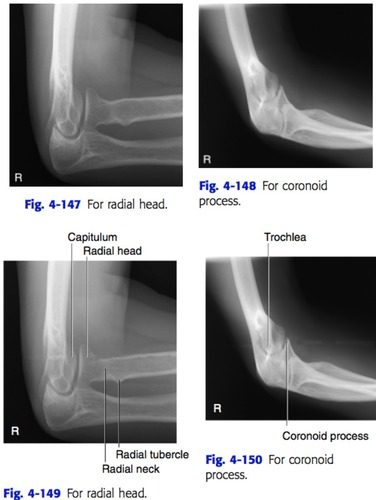

medial rotation of the elbow best shows the_____ process

lateral rotation best shows the _____ ____and_____

coronoid process

radial head and neck

Coyle method for elbow

to see radial head, point tube 45° toward/away from shoulder

to see coronoid proc, point tube 45° toward/away from shoulder

toward

away